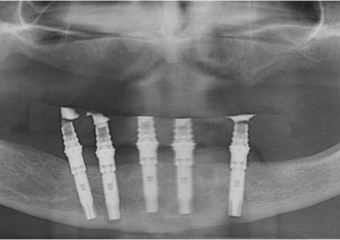

Rx após extração dos dentes e instalação de 05 implantes e prótese fixa imediata